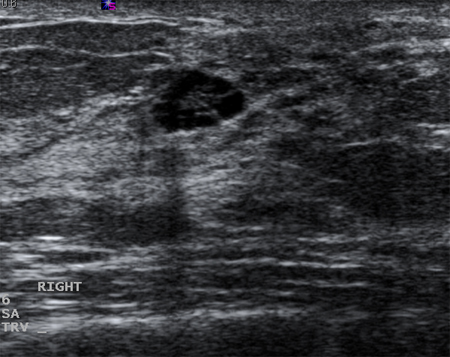

Ultrasonographic image of a complex cyst

Courtesy of Dr Lane Roland, University of Louisville; used with permission